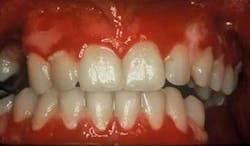

Clinical impressions: As you begin your oral assessment, you note the buccal mucosa and gingiva are erythematous with some ulceration and erosion. The erythema is very prominent at most marginal gingival areas. The tissue bleeds with very little pressure (see figure 1). You also notice that his lips appear ulcerated and crusted (see figure 2).

Early treatment is crucial in controlling pemphigus vulgaris. Sirois, et al. (2000) reported that more than 50 percent of patients in their study sought initial care from their dental clinician. Just as pemphigoid (March 2007) is often characterized as desquamative gingivitis (a general term), this is true also for pemphigus vulgaris depending upon the severity of the disease. The tissue involved is erythematous and ulcerated (see figure 1). Bullae may be present and they rupture to form painful erosions. The borders of the erosions are often ragged and painful. Depending upon the type of pemphigus, the lesions may appear to have vegetations or scales on the surface.